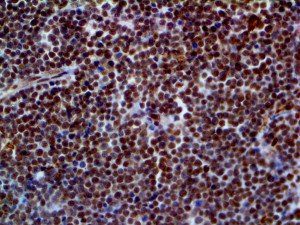

It is the ICU physician who is most likely to witness one of the deadliest manifestations of the abnormal immunological response, the cytokine storm syndrome (CSS). This response is also referred to by some as the cytokine release syndrome (CRS). CSS is characterized by continuous activation and expansion of macrophage and lymphocyte populations, which secrete large amounts of cytokines, causing the cytokine storm. This massive cytokine release is akin to hemophagocytic lymphohistiocytosis (HLH) disease, a syndrome characterized by initial unchecked and persistent activation of cytotoxic T lymphocytes and NK cells.

Clinical and laboratory manifestations of HLH include fever, enlarged liver and/or spleen, neurologic dysfunction, coagulopathy, liver dysfunction, cytopenias (i.e., low levels of erythrocytes, leukocytes, and/or platelets), hypertriglyceridemia, hyperferritinemia, hemophagocytosis, and eventually diminished NK cell activity as the immune system becomes progressively paralyzed. HLH can be familial (primary HLH) or secondary to another disease process (sHLH), such as rheumatic disease, in which it is referred to as macrophage activation syndrome (MAS, characterized by elevated ferritin).